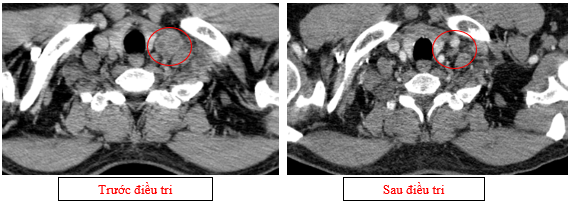

Hình 07: Hạch thượng đòn trái giảm đáng kể kích thước, từ 22mm còn 7mm sau điều trị.

-         Chụp cắt lớp vi tính lồng ngực (11/2025): Màng phổi vùng rốn phổi trái dày,dày tổ chức kẽ vùng ngoại vi đáy phổi hai bên. Màng phổi trái có vài nốt đặc ngấm thuốc nốt lớn nhất kích thước 17x15mm. Khoang màng phổi hai bên không có dịch – khí (Tổn thương giảm đáng kể so với phim chụp 08/2025). Trung thất, rốn phổi hai bên, hố thượng đòn trái có vài hạch, hạch lớn nhất kích thước 12x6mm. Vài nốt đặc xương rải rác thân đốt sống, các cung xương sườn hai bên.